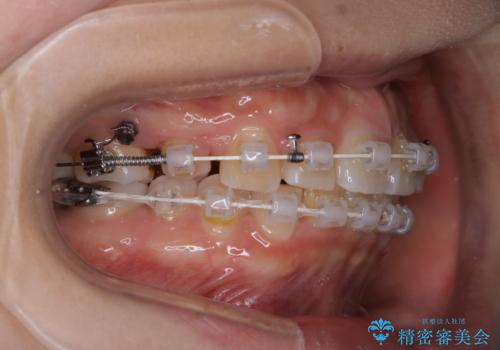

- 矯正装置

- 審美装置(ワイヤー)

- 治療期間

- 3年

- 治療回数

- 30回以上

当初は上顎前歯のみの部分矯正をご希望されていましたが、部分的に前歯のみを並べると出っ歯感がつよくなり、食事もしづらくなる可能性をお伝えしました。全顎的な矯正治療により、審美的、機能的な歯並びとなりました。